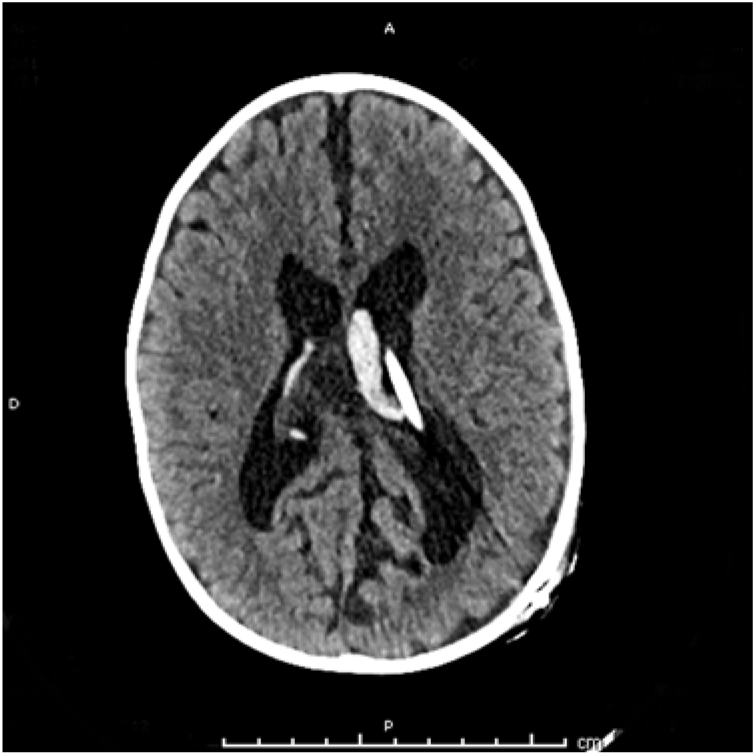

Figure 1: T2-weighted axial cerebral MRI demonstrating CP obstructing an otherwise clear proximal catheter tip in the occipital horn of the left lateral ventricle in an 18-month-old boy.

An 18-month-old boy known for a Chiari II malformation with shunted hydrocephalus was seen in clinic for progressive macrocrania. Shunt series and ophthalmologic exam were within normal limits. A cerebral MRI was performed and compared with previous imaging and showed an increase in ventricular dilation caused by hypo-intense CP on T2-weighted MRI obstructing an otherwise clear proximal catheter tip in the occipital horn of the left lateral ventricle (Figure 1.) The patient was taken to the operating room for proximal shunt revision. Resistance was felt while attempting to remove the catheter tip, due to the underlying CP. The tissue was cauterized using a monopolar on the shunt stylet. Upon cauterization, CSF flow through the catheter increased substantially suggesting the CP retracted from the catheter and the catheter was removed with slight resistance. Despite the coagulation, significant bleeding was observed from the insertion site after catheter removal. Ventricular endoscopy was then performed through the same burr hole and showed considerable ventricular hemorrhage (Figure 2) which was subsequently removed endoscopically. After homeostasis was achieved, a new ventricular catheter was inserted and connected to the valve. Inspection of the removed catheter was remarkable for CP both enveloping the tip and entering it (Figure 3). Post-operative course was uneventful, although the patient was kept for observation for four days because of the intraventricular hemorrhage.

CP is a frequently cited cause of obstructive, non-infectious shunt dysfunction.Reference Harris and McAllister2 However, radiological demonstration of CP obstruction has not been well demonstrated in the literature, suggesting that it may be a rare finding. One case report captured the process of occlusion in a neonate, showing real-time sonographic transient occlusion of the ventricular catheter tip by CP.Reference Mao, Agarwal, Zuccoli and Tyler-Kabara4 In a 2012 study by Singh and colleagues providing in-vivo endoscopic observations in 53 patients (mean age 13.3 years, range from 2 months to 60 years) undergoing endoscopic third ventriculostomy for shunt dysfunction, CP was seen blocking the catheter in 4 (7%) patients.Reference Singh, Saxena, Jagetia, Singh, Tandon and Ganjoo5 Our report adds to these findings, demonstrating the radiological appearance of CP causing CSF shunt dysfunction on MRI (Figure 1). The intraventricular hemorrhage which occurred in this patient despite coagulation of the plexus highlights the importance of its preoperative recognition and/or intraoperative identification.